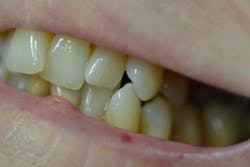

Figure 3: Maxillary anterior right

Her periodontal probing depths ranged from 2 mm to 6 mm, with as much as 4 mm of recession noted in some areas. Tooth No. 19 had a fractured off DL cusp to the gumline with decay close to the nerve; No. 29 had deep DO decay that would require endodontic treatment, buildup, and a crown to repair or possibly extraction; and No. 31 was unrestorable with buccal decay to the nerve, through the furcation, and at the bone level (figures 1–6). Faced with that treatment plan, she would also need four quads of scaling and root planing with anesthetic. We were able to coordinate the schedule to extract No. 31 directly after her periodontal treatment while she was still anesthetized.